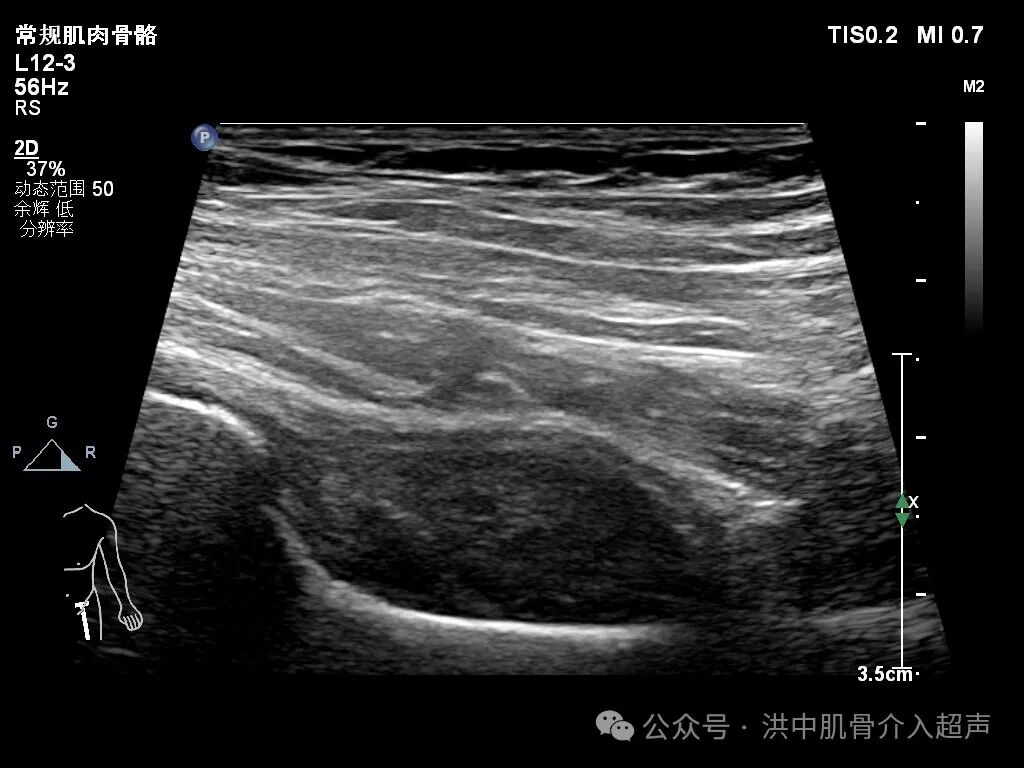

病例:23岁女性患者,左侧髋关节疼痛不适一月余,行走困难就诊。既往有过髋关节滑膜炎及治疗病史。

超声显示:股骨颈前间隙滑膜增生并少许积液。CDFI:少许点状血流信号。

结合临床症状及超声表现,考虑髋关节滑膜炎并积液。经与患者沟通同意后行超声引导下抽吸、注射治疗。

后期回访患者改善好转。